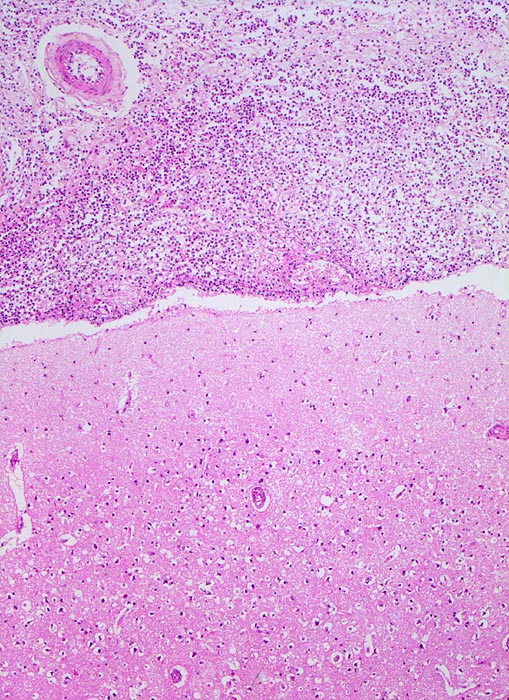

Eitrige Leptomeningitis

Über der Grosshirnrinde (unten im Bild) ist der Subarachnoidalraum ausgeweitet und mit Eiter angefüllt.

Bronchopneumonie. Nachweis von Pneumokokken im Abstrich von der Hirnoberfläche und von der Lunge.

Die Ausbreitung bakterieller Meningitiserreger geschieht meist hämatogen. Im vorliegenden Fall war die Pneumonie Ausgangspunkt für die Meningitis. Als weitere Infektionsquellen kommen in Frage Infekte im HNO Bereich (Ausbreitung per continuitatem ausgehend von Sinusitis oder Mastoiditis), neurochirurgische Eingriffe, offene Hirnverletzungen, infizierter ventriculoperitonealer Shunt...